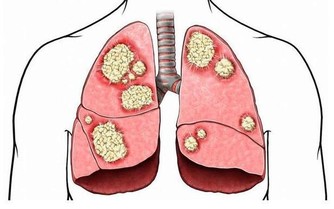

熱衰竭,由高溫引起的相對溫和的健康問題,可以是高溫暴露體液補給不足,或身體水鹽礦物質不平衡,經由幾天的連續積累發展而來。

1怎樣識別

症狀包括眩暈頭痛、噁心據吐、大量出汗臉色蒼白,體溫稍高或正常、極度虛弱或疲倦、肌肉痙、昏厥等患者如有反、腹瀉或嘔吐,可能會導致熱射病。老年人、血壓患者、在高溫環境中進行重體力勞動或長跑等劇烈運動的人更易發生熱衰竭。

2怎樣處理

飲用涼爽且不含酒精的飲料;沖涼水澡威擦拭身體;如果症狀持續不好轉或繼續惡化,及時尋求醫療救助。